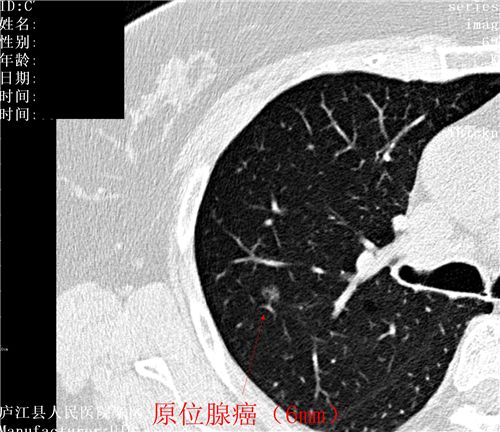

肺癌目前发病率排名第一,肺癌5年生存率任然低于20%,为什么会这么低?就是发现肿瘤时就是晚期肺癌,晚期肺癌无论是手术还是放化疗治疗效果就会差很多。如何能够早期发现?目前国际上达成专家共识,那就是低剂量螺旋CT检查,通俗易懂地说就是接受最小的辐射剂量,达到最好的早期肺癌的诊断效果,要知道,早期肺癌是不痛不痒,没有任何症状的,要想查出它只有CT检查,照张胸片那就意味着是“凶片”。胸部低剂量CT让早期肺癌无处逃遁!

图片展示:健康体检中发现的肿瘤